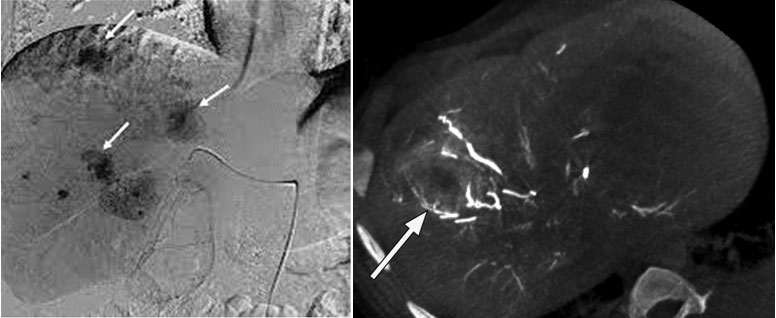

TACE is a targeted liver cancer treatment that delivers chemotherapy directly into the tumor’s blood supply.

A thin catheter is inserted through the groin or wrist artery

Chemotherapy drugs are delivered directly to the liver tumor

Blood supply to the tumor is blocked (embolization)

Tumor cells are deprived of oxygen and nutrients

High concentration of chemotherapy at tumor site

Minimal effect on the rest of the body

Effective for intermediate-stage liver cancer

Can shrink tumors and slow disease progression